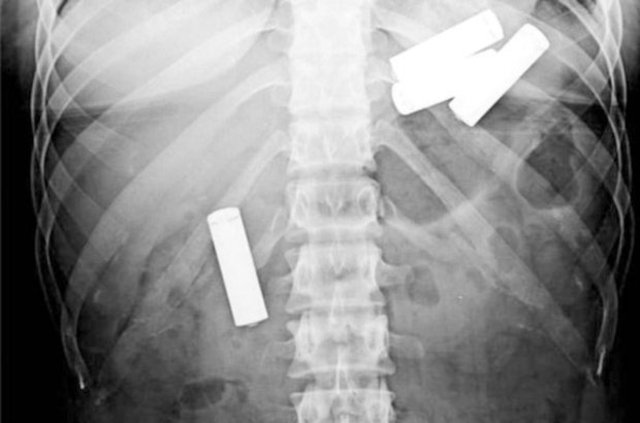

Cumhuriyet Üniversitesi (CÜ) Tıp Fakültesi Araştırma ve Uygulama Hastanesi Göğüs Cerrahisi Anabilim Dalı Servisi'nde insanların yanlışlıkla yuttuğu cisimlerden oluşturulan koleksiyon, görenleri hayrete düşürüyor.

Operasyonla mideden ya da nefes borusundan çıkan parçalar zaman zaman hekimleri bile şaşırtıyor.

Aralarında iğne, metal kolye, vida, protez diş, dikiş iğnesi, kemik parçası, pisi pisi otu, çivi ve akasya dikeni de bulunan cisimleri koleksiyon yapan hekimler, vatandaşların ağızlarına aldıkları şeylere dikkat etmeleri gerektiğini dile getiriyor.

Prof. Dr. Ekber Şahin, AA muhabirine yaptığı açıklamada, Sivas'ta son yıllarda yetişkinler ve çocukların yuttuğu yaklaşık 700 civarında yabancı cismi insanların mideleri ve nefes borularından başarıyla çıkardıklarını söyledi.

Operasyonlarda yabancı cisimlerle karşılaştıklarını ve şaşırdıklarını anlatan Şahin, "Çıkardığımız bu cisimlerin bir kısmıyla koleksiyon oluşturduk. Yıllardır çıkardıklarımız biriktirdiklerimizin 20-30 katı kadar" dedi.

Çıkardıkları cisimler arasında iğneler, metal kolyeler, vidalar, protez dişler, dikiş iğneleri, kemik parçaları, pisi pisi otları, çiviler ve akasya dikeni bulunduğunu kaydeden Şahin, "Bir insan akasya dikenini nasıl yutabilir diye çok şaşırıyoruz.